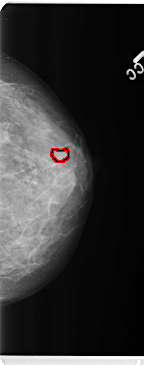

FILE: B_3359_1.LEFT_CC.OVERLAY

TOTAL_ABNORMALITIES 1

ABNORMALITY 1

LESION_TYPE MASS SHAPE IRREGULAR MARGINS CIRCUMSCRIBED-OBSCURED

ASSESSMENT 4

SUBTLETY 3

PATHOLOGY BENIGN

TOTAL_OUTLINES 1

BOUNDARY